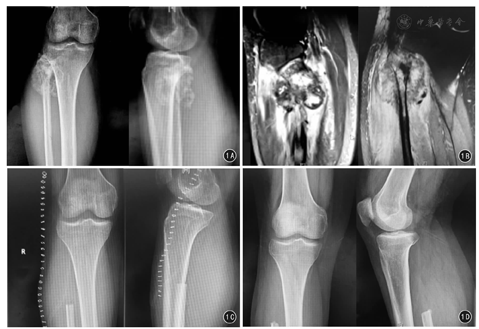

纳入2007年1月—2016年1月解放军东部战区总医院骨科腓骨近端骨肉瘤患者18例,其中男11例、女7例,中位年龄17(8~38)岁;左侧10例、右侧8例,Enneking外科分期ⅡB期17例、Ⅲ期1例。入院后均行患肢X线片、CT、MRI及胸部CT检查。X线片和CT可见腓骨近端骨质破坏,髓腔内浸润,多数患者可见日光样或放射状骨膜反应,伴有软组织肿块,其内可见高密度瘤骨。MRI可见腓骨近端被肿瘤浸润破坏后信号增高、骨皮质菲薄、中断,破坏区软组织占据。T1WI呈中低信号,T2WI呈中等偏高信号,瘤周水肿T2WI为高信号。

18例患者全部获得随访,随访时间7~120个月。8例出现肺部转移,死亡5例,另外3例患者截止末次随访时仍带瘤生存,皆进行口服阿帕替尼靶向治疗中。5例死亡患者中:1例入院即发生肺部转移,给予术后MTX化疗一次后患者肿瘤继续生长,2周后给予截肢手术,术后7个月死于肺衰竭;2例外院行非标准手术,导致局部间室污染,入院即行截肢手术,术后继续给予辅助化疗,分别于术后5、10个月发生肺部转移,并分别于术后8、12个月死于呼吸衰竭;2例接受Malawer type Ⅰ手术患者分别于术后18、36个月死于广泛肺转移引起的呼吸衰竭。15例保肢患者中1例出现术后伤口感染,给予积极加强换药,伤口正常愈合。复发4例皆为Malawer type Ⅰ手术患者,发现复发后均立即给予膝上截肢术。5例出现腓总神经损伤:其中2例患者术后2周神经麻痹症状逐渐自行好转,分别于术后3、7个月主诉症状基本消失;1例轻度跛行;2例Ⅱ型切除患者出现足下垂需佩踝关节支具行走。15例保肢手术患者无一例出现术后膝关节不稳症状表现,术后3个月MSTS功能评分显示术后膝关节功能良好11例、一般2例、差2例。患者具体资料见表1。典型病例见图1。